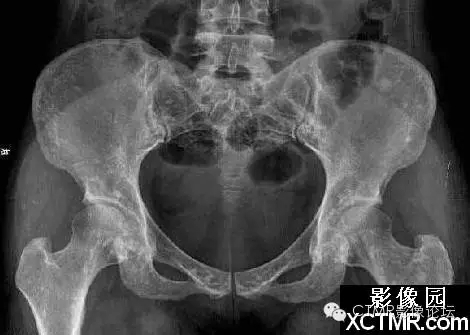

骨斑點癥是一種罕見病,可無任何臨床癥狀。是由于骨內(nèi)具有彌漫性斑點狀致密骨質(zhì)而得名。既往文獻曾稱局限性骨質(zhì)增生癥、彌漫性濃縮性骨病、家族性彌漫性骨硬化癥、點狀致密骨病等。特點為松質(zhì)骨內(nèi)有彌漫性圓點狀致密影。臨床上可無任何癥狀,一般為X線檢查所發(fā)現(xiàn)??梢娪谌魏文挲g,男多于女。血鈣、磷正常。

骨斑點癥具有以下特點:

(1)本病無臨床癥狀,均為查體或檢查其它病時發(fā)現(xiàn)本病。

(2)本病與年齡性別無關,本組從22~58歲,文獻報道年齡從4個月~90歲均有發(fā)病。

(3)病灶呈彌漫性多發(fā)的密度增大的圓形、橢圓形、圓圈狀、結節(jié)狀陰影,其形態(tài)走行,部分與骨的長軸一致。

(4)病灶多累及長骨的兩端,密集于干骺端及骨骺,以及骨盆、手、足及不規(guī)則骨。越靠近關節(jié)病灶越密集,且密度越濃。病灶可相互融合成片而遮蓋正常骨組織。

(5)密度增濃的斑點狀病灶的邊緣不甚清晰銳利,越靠近中心部位密度越濃,邊緣部位密度略淡。

(6)病灶侵及骨的松質(zhì)骨。骨膜及關節(jié)軟骨不受侵犯,故關節(jié)間隙光整清晰。

(7)ECT檢查見顯影后骨骼放射性分布不均勻,骨松質(zhì)內(nèi)有多個大小不等的骨鈣化灶。骨顯像對應性放射性增強。據(jù)上述表現(xiàn)視全身骨顯像多處骨代謝增強灶,為骨質(zhì)代謝異常。

(8)本病應與成骨性轉(zhuǎn)移相鑒別。成骨性轉(zhuǎn)移首先應有原發(fā)性病灶并轉(zhuǎn)移灶呈單發(fā)或散在多發(fā)性骨質(zhì)增濃病灶,無密集對稱性。其病灶直徑均較大,直徑一般在1.0cm以上,同時伴有明顯的疼痛癥狀。與本病鑒別不難。還應與蠟淚樣骨相鑒別。